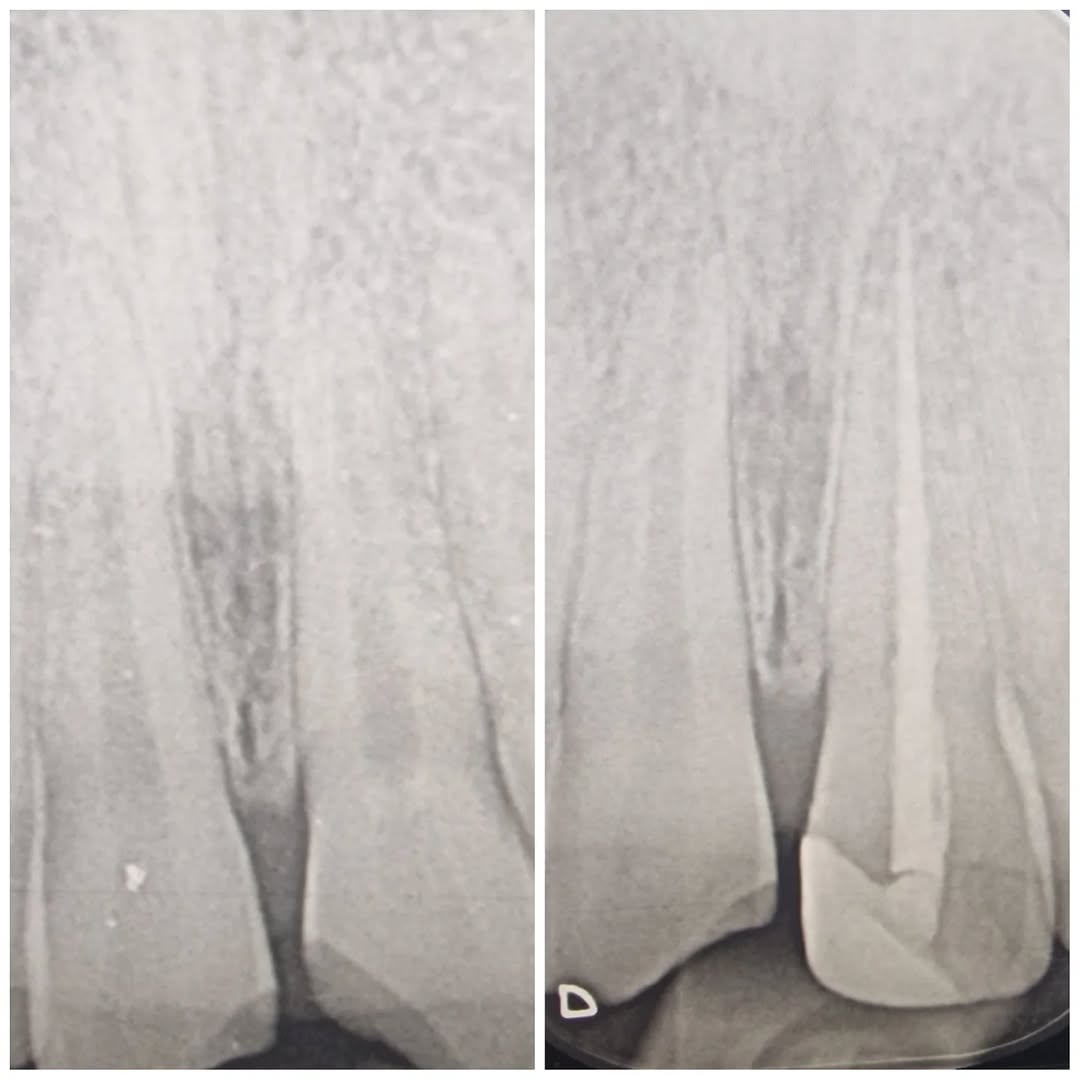

16yo patient came in with excruciating pain due to traumatic fractures on upper anteriors. UR1 was asymptomatic, UL1 had the pulp chamber opened. RCT made with ProTaper Wave One Gold, single session and the final restoration was made with composite ????

11